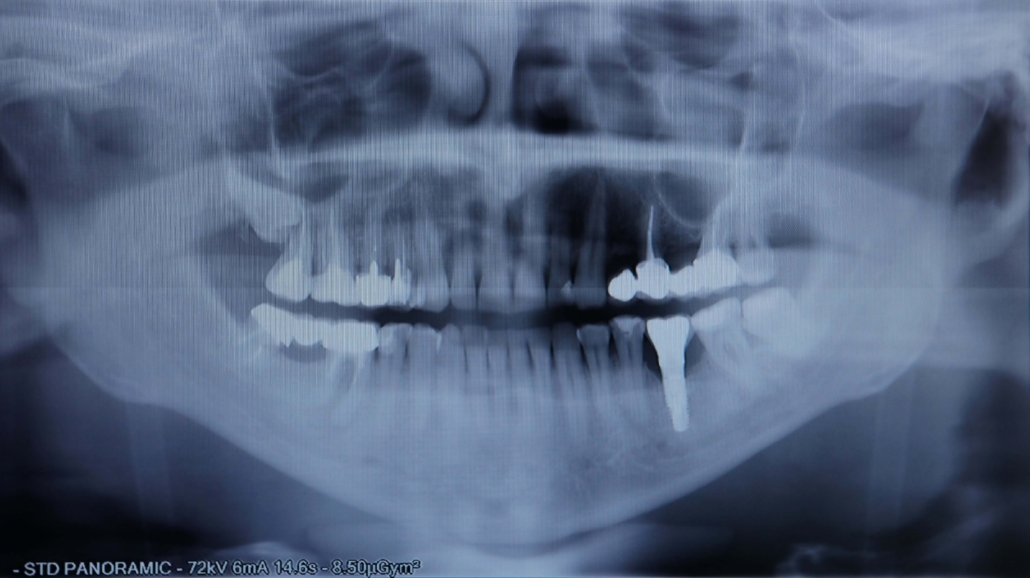

Çocuklarda diş ağrısı genellikle çürük, diş eti enfeksiyonu veya travma gibi nedenlerden kaynaklanır. Ağrının sebebini anlamak ve doğru müdahalede bulunmak önemlidir.

Diş Çürükleri: Dişte hassasiyet ve zonklama şeklinde ağrı yapabilir.

Diş Travmaları: Düşme veya darbe sonucu oluşan çatlak veya kırıklar ağrıya neden olabilir.